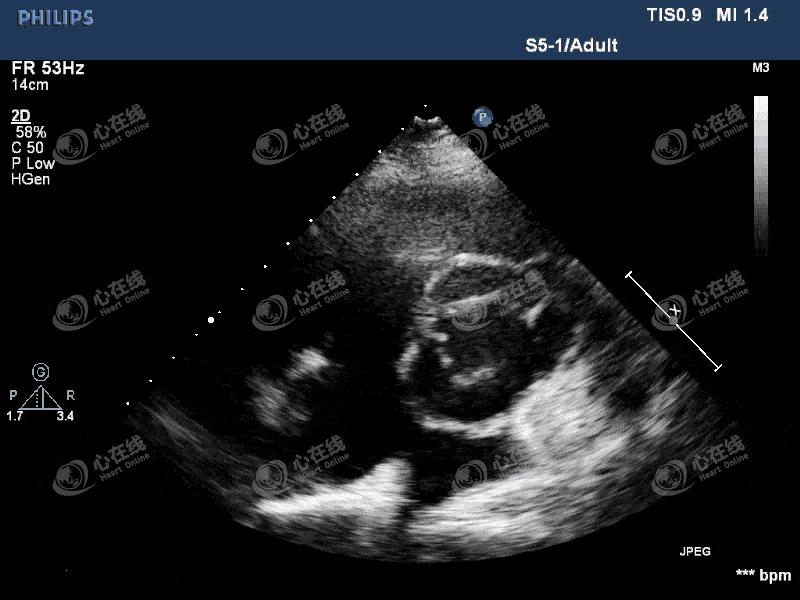

图4 大动脉短轴切面:主动脉瓣机械瓣缝合环外周可见蜂窝状无回声区环绕,机械瓣环活动度增大,机械瓣启闭正常。